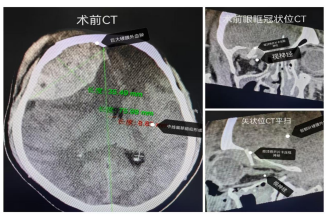

2025年11月22日21时57分,云南籍游客李先生(化名)在小金县四姑娘山景区附近遭遇交通事故,被紧急送至小金县人民医院。经检查,患者已陷入昏迷,右侧瞳孔散大,对光反射消失,头颅CT显示其颅内大量出血并已形成脑疝,同时存在视神经严重受压——这是神经外科最危急的情况之一,死亡率极高。

“患者双侧瞳孔不等大,脑疝形成,必须立即手术!“小金县人民医院急诊外科医生郭伟在初步判断后,一方面组织本地医护力量进行紧急降颅压处理,维持生命体征;另一方面,迅速通过“川甘青颅脑疾病救治群”上传患者相关病历资料、影像学图片及实时生命体征数据,向州级医疗中心发出紧急会诊请求。

手术室里,一场与死神的较量紧张展开。神经外科团队提前做出手术预案——既要清除颅内血肿、解除脑疝对生命中枢的压迫,又要在显微镜下精细操作,为被骨折片卡压的视神经“松绑”。

“颅内出血量大,术中不仅要清除血肿还要控制好出血。”主刀医生回忆道,“最关键的视神经减压及颅底修补环节,手术团队在显微镜下以毫米级的精度,一点一点剥离骨折片与视神经的粘连。“经过近4个小时的精细操作,“视神经的压迫解除了,瞳孔检查较术前略有缩小!手术成功完成。